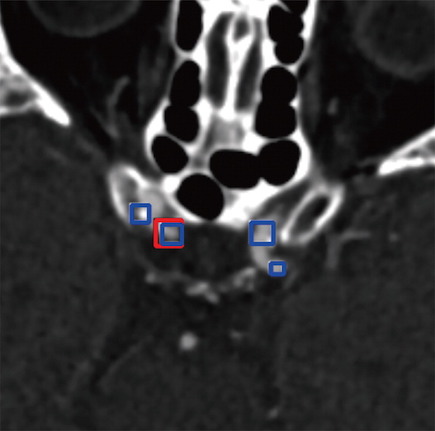

La détection et la caractérisation des anévrismes cérébraux sont essentielles, car le risque de rupture dépend de la taille, de la forme et de l'emplacement de ceux-ci. L'angioscanner est généralement le premier choix pour évaluer les anévrismes cérébraux. L'examen est très précis, mais les anévrismes cérébraux peuvent passer inaperçus de prime abord, en raison de leur petite taille et de la complexité du réseau vasculaire cérébral.

Le deep learning offre un énorme potentiel en tant qu'outil complémentaire pour une interprétation plus précise des anévrismes cérébraux. Dans cette étude, le Dr Long et ses collègues ont développé un algorithme entièrement automatisé et hautement sensible pour la détection des anévrismes cérébraux sur les images d'angioscanner. Ils ont utilisé des angiogrammes de plus de 500 patients pour former le système de deep learning, puis ils l'ont testé sur 534 autres angioscanners incluant 649 anévrismes.

L'algorithme a détecté 633 des 649 anévrismes cérébraux pour une sensibilité de 97,5%. Il a également trouvé huit nouveaux anévrismes qui ont été négligés lors de l'interprétation initiale. L’analyse statistique a révélé que l’aide au diagnostic était la plus prononcée chez les radiologues moins expérimentés. Les résultats suggèrent que l'algorithme utilisé est prometteur en tant qu'outil de soutien pour la détection des anévrismes cérébraux avec un potentiel pour être utilisé cliniquement comme deuxième avis lors de l'interprétation des images d'angioscanner cérébral. Pour le Dr Long, il présente un certain nombre d'avantages car l'ordinateur n'est pas influencé par des facteurs tels que le niveau d'expérience, le temps de travail et l'humeur qui affectent les performances humaines.

Des résultats à améliorer notamment dans les régions péri-osseuses

Il y trouve cependant certaines limites, comme l’omission de très petits anévrismes ou d’anévrismes situés à proximité de structures de densité osseuse ou quelques rares faux positifs. « En termes simples, le système de deep learning est destiné à aider les lecteurs humains, pas à les remplacer, conclut le Dr Long. À l'heure actuelle, le rôle de ce système d'apprentissage en profondeur, qui a été formé pour reconnaître les anévrismes, est de donner des suggestions au lecteur humain pour améliorer ses performances et réduire les erreurs. Le travail combiné du lecteur humain et du système informatique améliore la précision du diagnostic pour le bien du patient. »